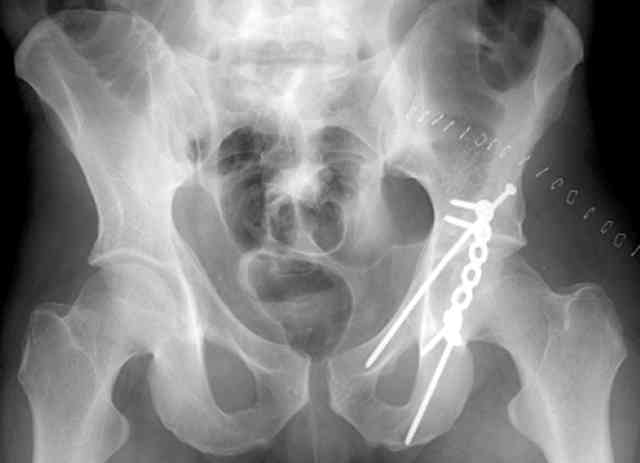

Same with a contoured pelvic reconstruction plate applied and tensioned.

Prone Iliac Oblique

The other oblique reveals the extra-articular implants.... you know the AC screw is extra-articular from the other views.